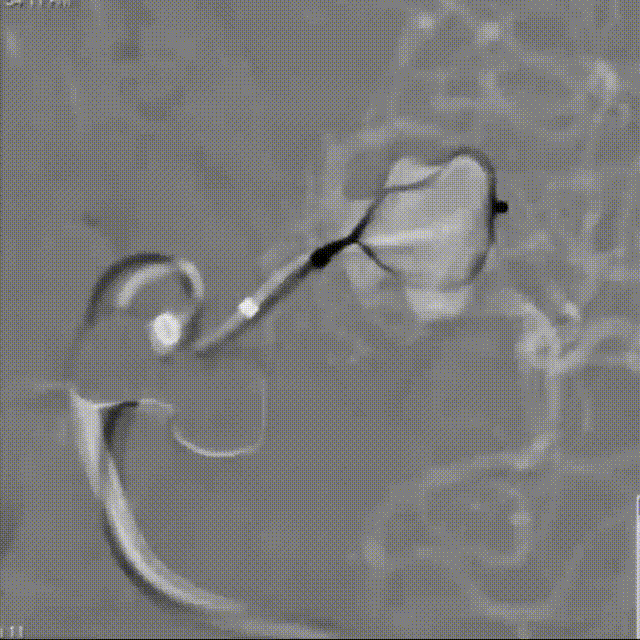

WEB™经由VIA™微导管缓慢推送至微导管头端。缓慢推出WEB™从种子至萌芽状态,继续向瘤腔内远端缓慢推送WEB™至萌芽至开花间状态;将WEB™送至瘤顶,固定WEB™推送杆回撤VIA™,WEB™完全释放。

经造影可见WEB™尺寸合适,贴合瘤壁。解脱后,再次造影可见动脉瘤瘤腔内有明显造影剂滞留。WEB™对分支血流有影响,使用支架保护分支。

术后6个月随访造影,WEB™充分栓塞,瘤颈残留,WEB™被压缩。